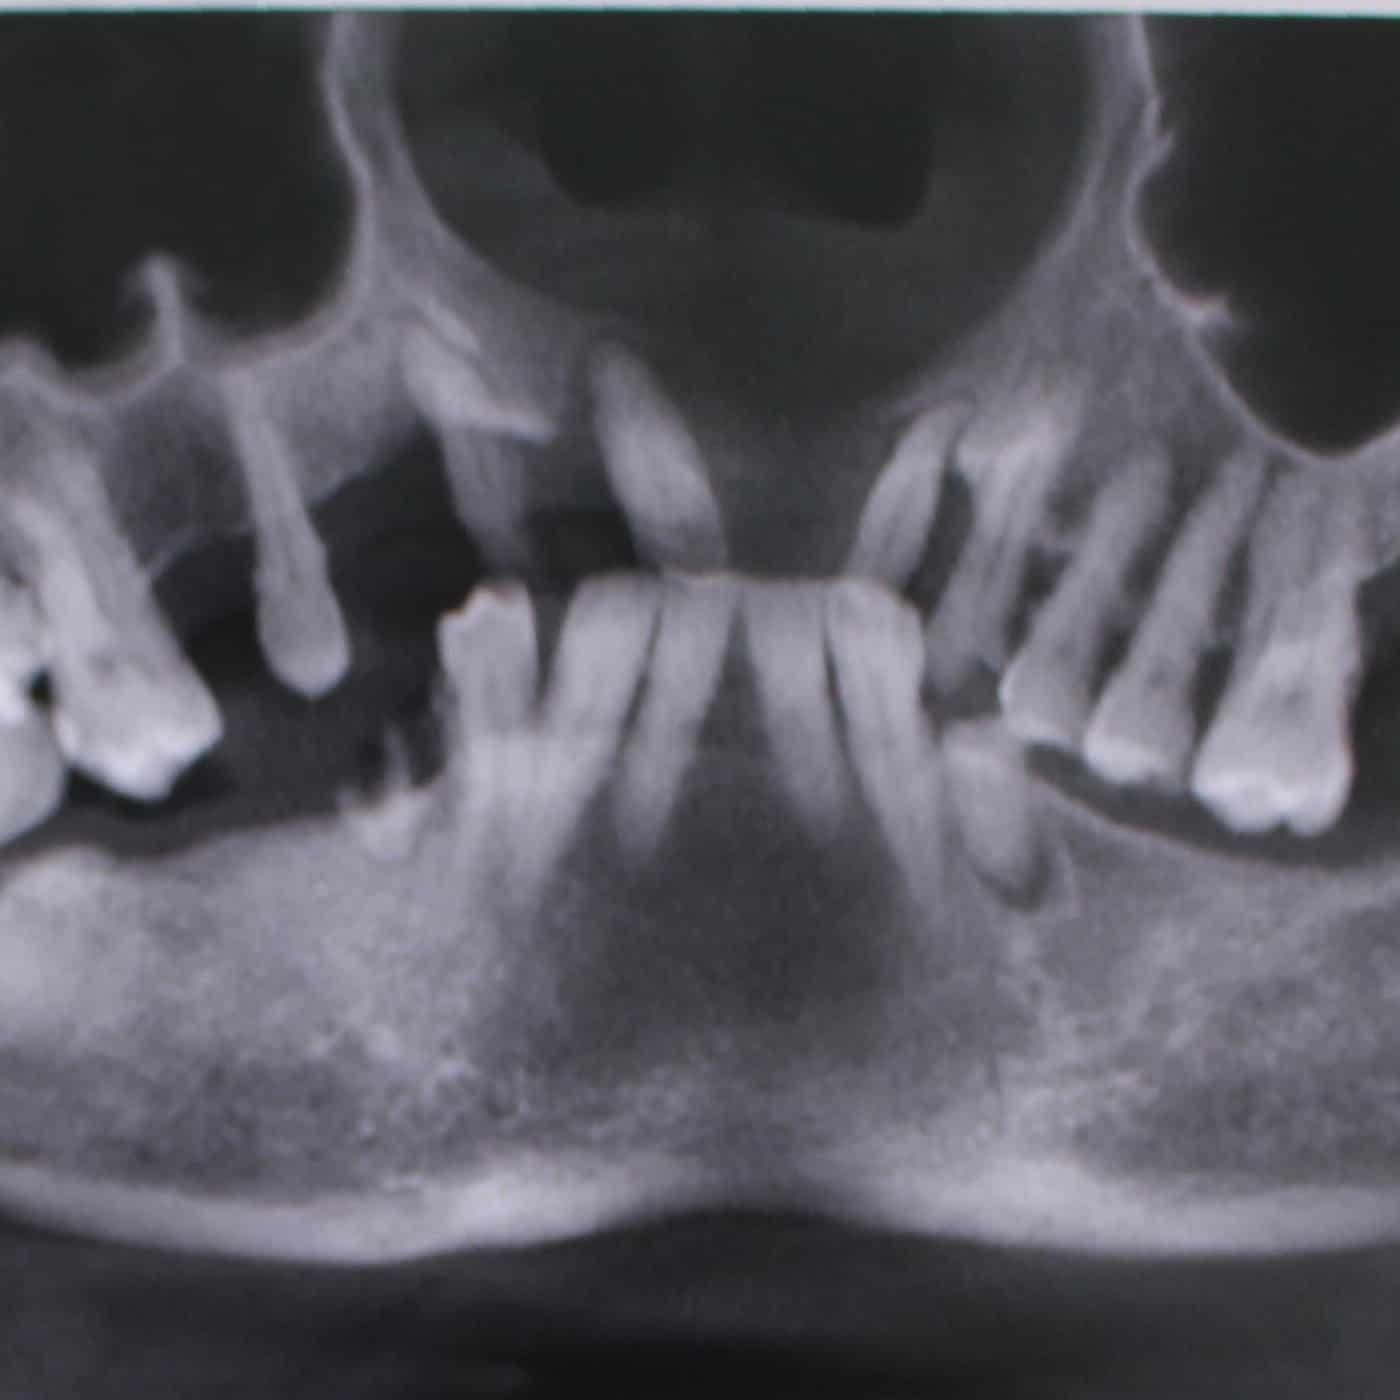

Trong trường hợp bệnh nhân dưới đây bị mất răng toàn hàm, trong thời gian gian và còn chịu áp lực của hàm tháo lắp nên xương hàm tiêu đi rất nhiều, nướu teo lại đáng kể.

Kết quả này được thể hiện rất rõ ràng trên kết quả chụp phim 3D cho biết mật độ, thể tích, chiều dài, chiều rộng của xương hàm. Bên cạnh đó, chụp phim 3D còn định vị được các dây thần kinh xung quanh xương hàm trên, hàm dưới và phát hiện các bệnh lý, tổn thương (nếu có).

Lúc này, việc thực hiện răng giả tháo lắp hay làm cầu răng sứ đều không đạt hiệu quả vì không tạo được độ khít sát thẩm mỹ và đảm bảo chức năng ăn nhai hoàn hảo.

Trong trường hợp này, chỉ có cấy ghép Implant mới có thể trồng lại răng đã mất chắc chắn và khắc phục tình trạng tiêu xương hàm. Bằng cách bác sĩ sẽ đặt chân răng nhân tạo (trụ Implant), sau đó gắn phục hình răng sứ khít sát ở trên thông qua khớp nối Abutment.